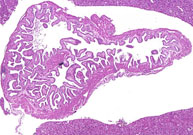

Normal gallbladder. An empty gallbladder of an adult mouse with a folded mucosa.